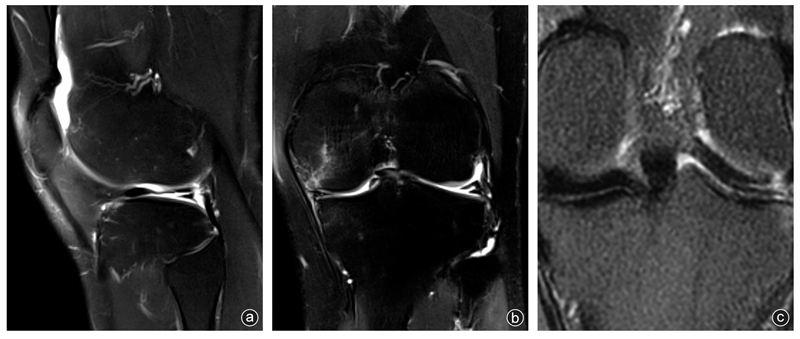

病人,男,19岁,左膝关节时常有伸屈活动时弹响,入院3周前军事训练时扭伤左膝关节,后出现肿胀,频繁出现关节绞锁、弹响并伴有疼痛。查体:左膝关节过屈过伸痛(+),外侧关节间隙压痛,麦氏征(+),左膝关节MRI提示外侧盘状半月板并水平分层撕裂(图1)。行关节镜下检查见半月板桶柄样撕裂并嵌顿于股骨髁间,外侧半月板为 Wrisberg 韧带型(图2 a-c),行盘状半月板成形,半月板后角胫骨止点重建固定,并将游离缘缝合固定于关节囊(图2 d-j)。术后1年复查MRI显示半月板愈合良好,左膝关节疼痛、弹响及绞锁症状消失(图2 k-l)。

图1 病人术前MRI影像学资料 a:术前矢状位MRI显示半月板体部及后角撕裂;b:术前冠状位MRI显示半月板水平撕裂;c:术前外侧半月板后根部冠状位MRI显示外侧半月板后根部与胫骨、关节囊无附着,呈Wrisberg韧带